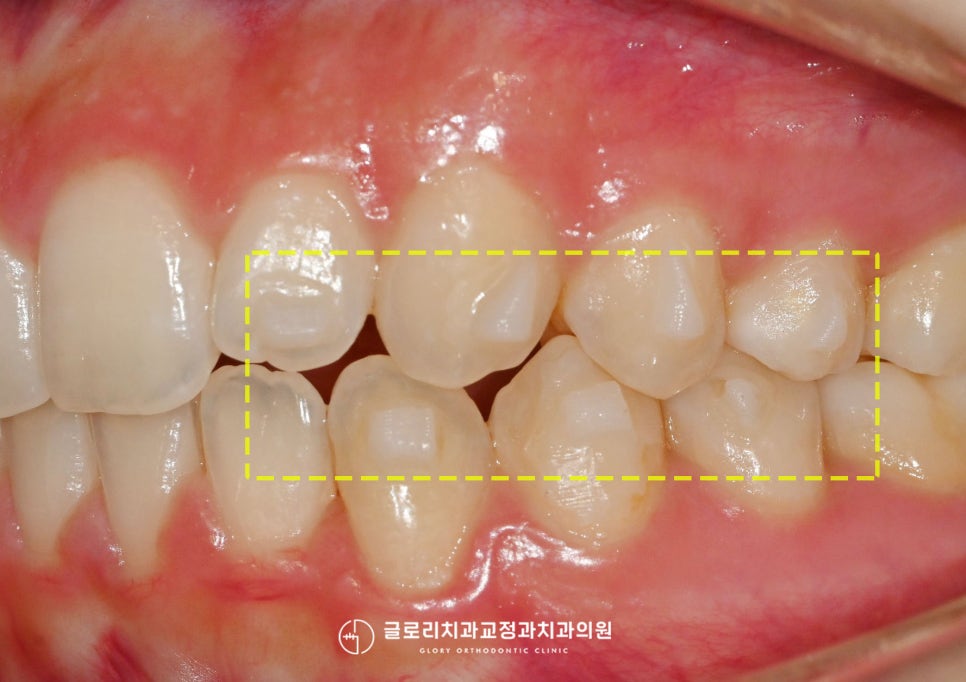

윗니 전치부의 가운데의 인접치로 측절치가

유독 이동한 모습이 눈에 띄었습니다.

앞으로 뻐드러짐과 동시에

살짝 회전된 듯한 형태도 보이는데요.

측면에서 보게 되면 이런 뻐드러짐이

더욱 눈에 띄어 튀어나온 듯한 느낌이 듭니다.

더군다나 앞니 쪽이다 보니

계속 신경이 쓰일 수밖에 없어

치아 재교정을 마음먹으셨다고 하셨습니다.